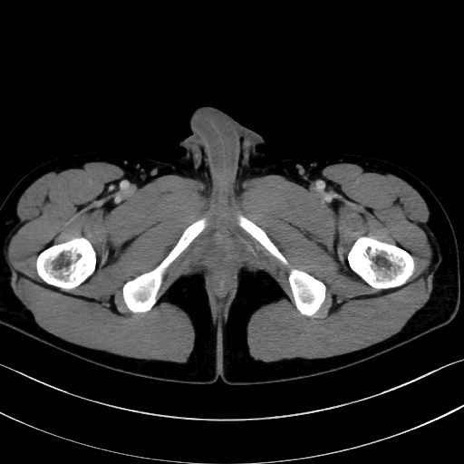

4. 深層外旋六筋(股関節の深部)

梨状筋 (Piriformis)

内閉鎖筋 (Obturator internus)

外閉鎖筋 (Obturator externus)

大腿方形筋 (Quadratus femoris)